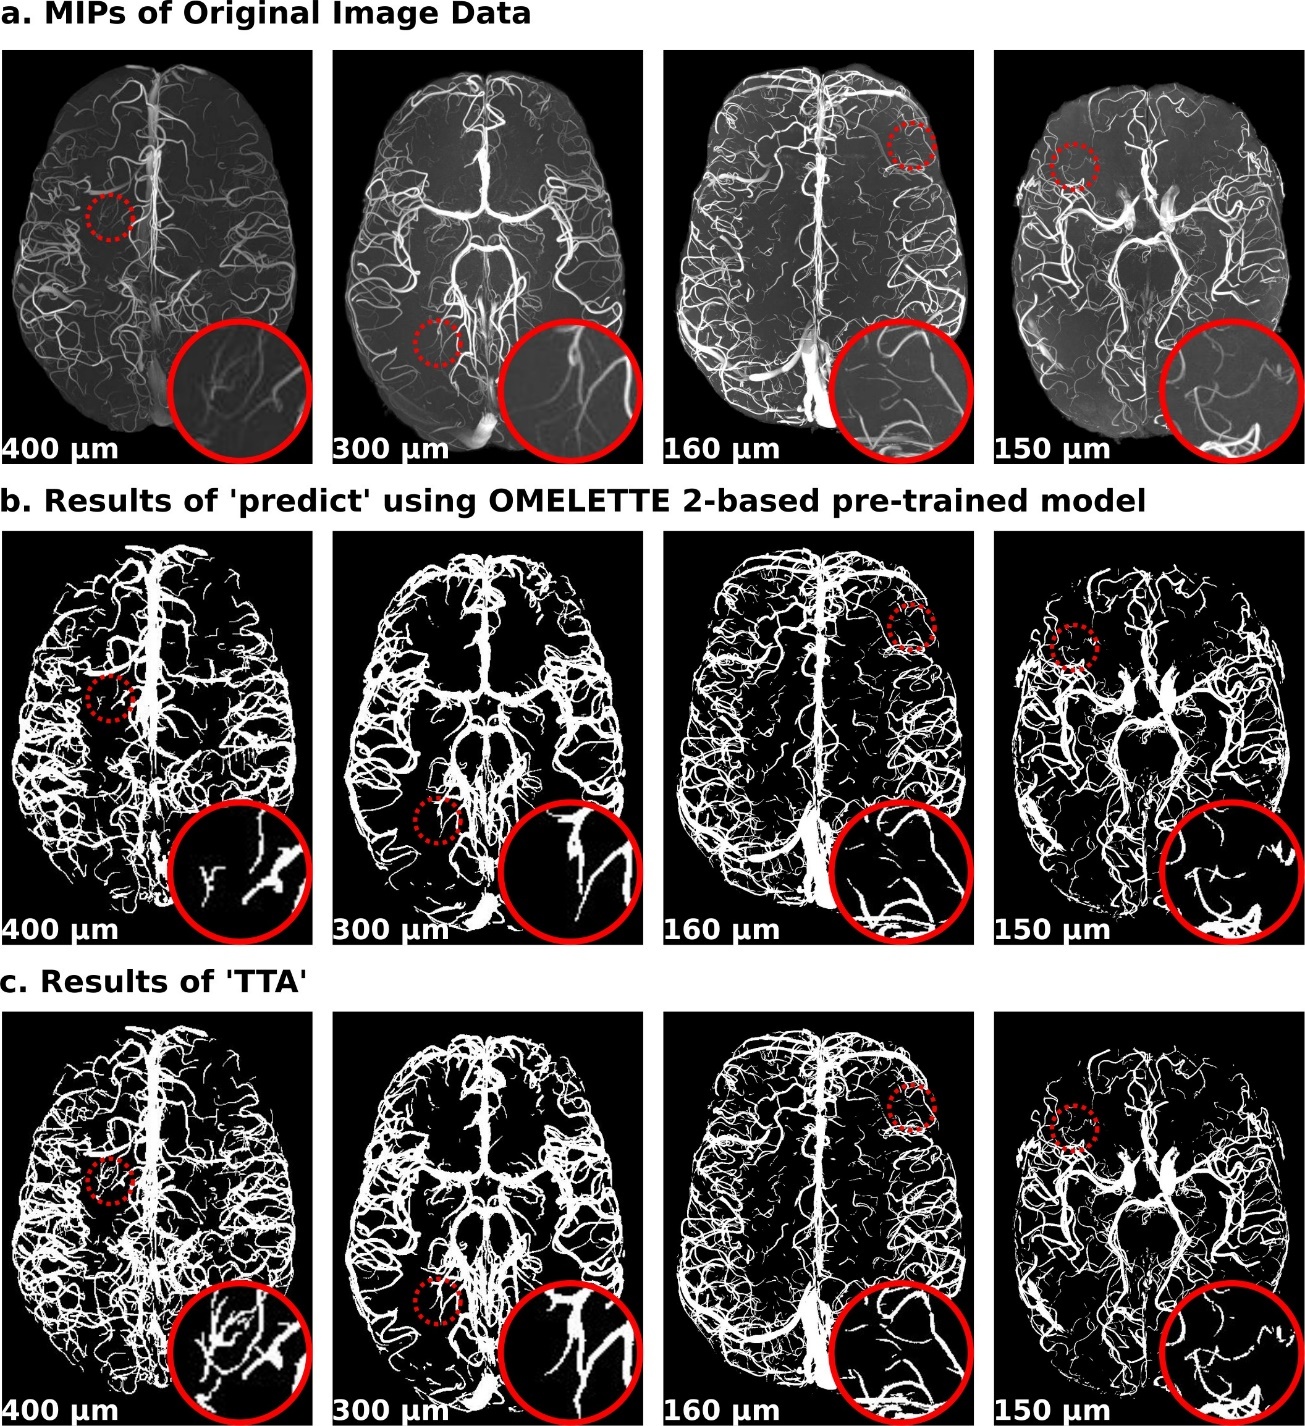

3.2. Experiment 2

Figure 3 demonstrates that TTA can offer additional segmentation improvement when pre-trained models are fine-tuned on automatically generated, imperfect proxy segmentations— for example, generated with predict. Figure 3a shows the MIP of the original input images, and Figure 3b shows the initial segmentation of the OMELETTE 2-based pre-trained model. Note how this pre-trained model cannot segment the smallest vessel shown in the ‘zoomed-in’ patches. Despite being imperfect, these segmentations can be leveraged as proxy segmentations for TTA. Accordingly, we found improved segmentation of the smallest vessels (see 400 µm and 300 µm images) and improved segmentation continuity (see 160 µm and 150 µm images) (Figure 3c).